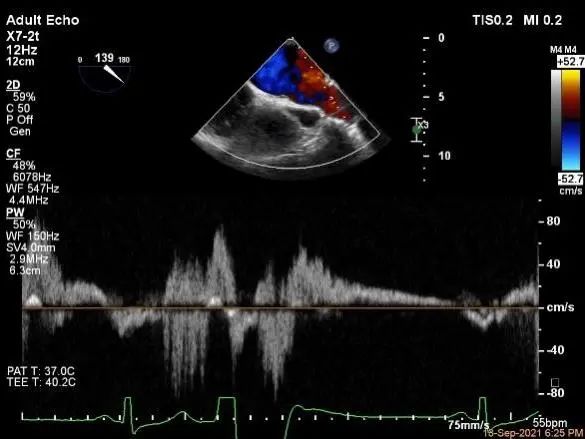

麻醉状态下肺静脉血流频谱

MVA:7.8cm2,平均跨瓣压差:1mmHg

根据Expand研究,有1/3以上的MR患者为复杂MR。本例患者为P1接近前交界区的腱索断裂,在MR评估方面,应该注意评估二尖瓣返流的具体受累区域、返流方向,血流束宽度,反流量分级及受累区域的最大宽度,以此作为制定手术策略的主要参考依据。脱垂宽度及血流束累及范围、有效返流口面积、平均跨瓣压差及瓣叶长度可以有效帮助术前判断夹子类型、大小及植入数量,对受累区域的定位还可以帮助确定房间隔穿刺的高度及范围。另外,对肺静脉血流频谱形态的采集,还可以辅助评估返流分级。该患者术前二尖瓣返流定量参数及肺静脉血流频谱均提示患者存在重度4级的返流。脱垂区域位于1区靠前交界处,提示穿刺高度可以在正常低限(4-5),该例患者术中穿刺高度4.08cm,基本符合手术方案要求。